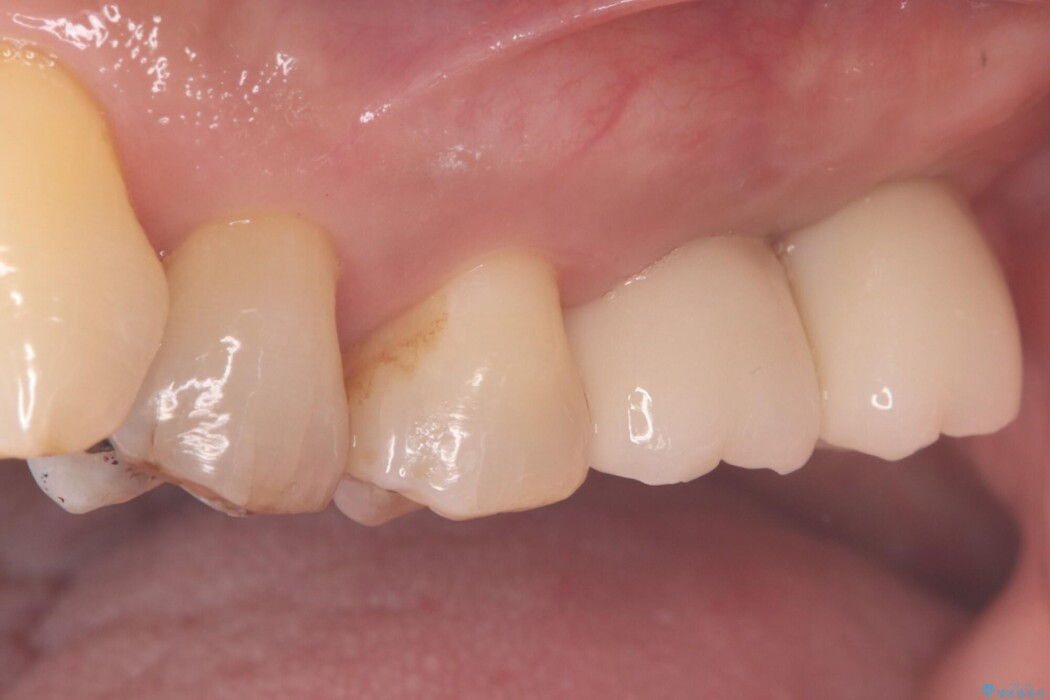

左上奥歯の欠損を、抜歯即時埋入を活用したインプラントで修復しました。

精密な位置決めと効率的な術式により、短期間でしっかり噛める喜びとお口全体の健康なバランスを取り戻すことができました。